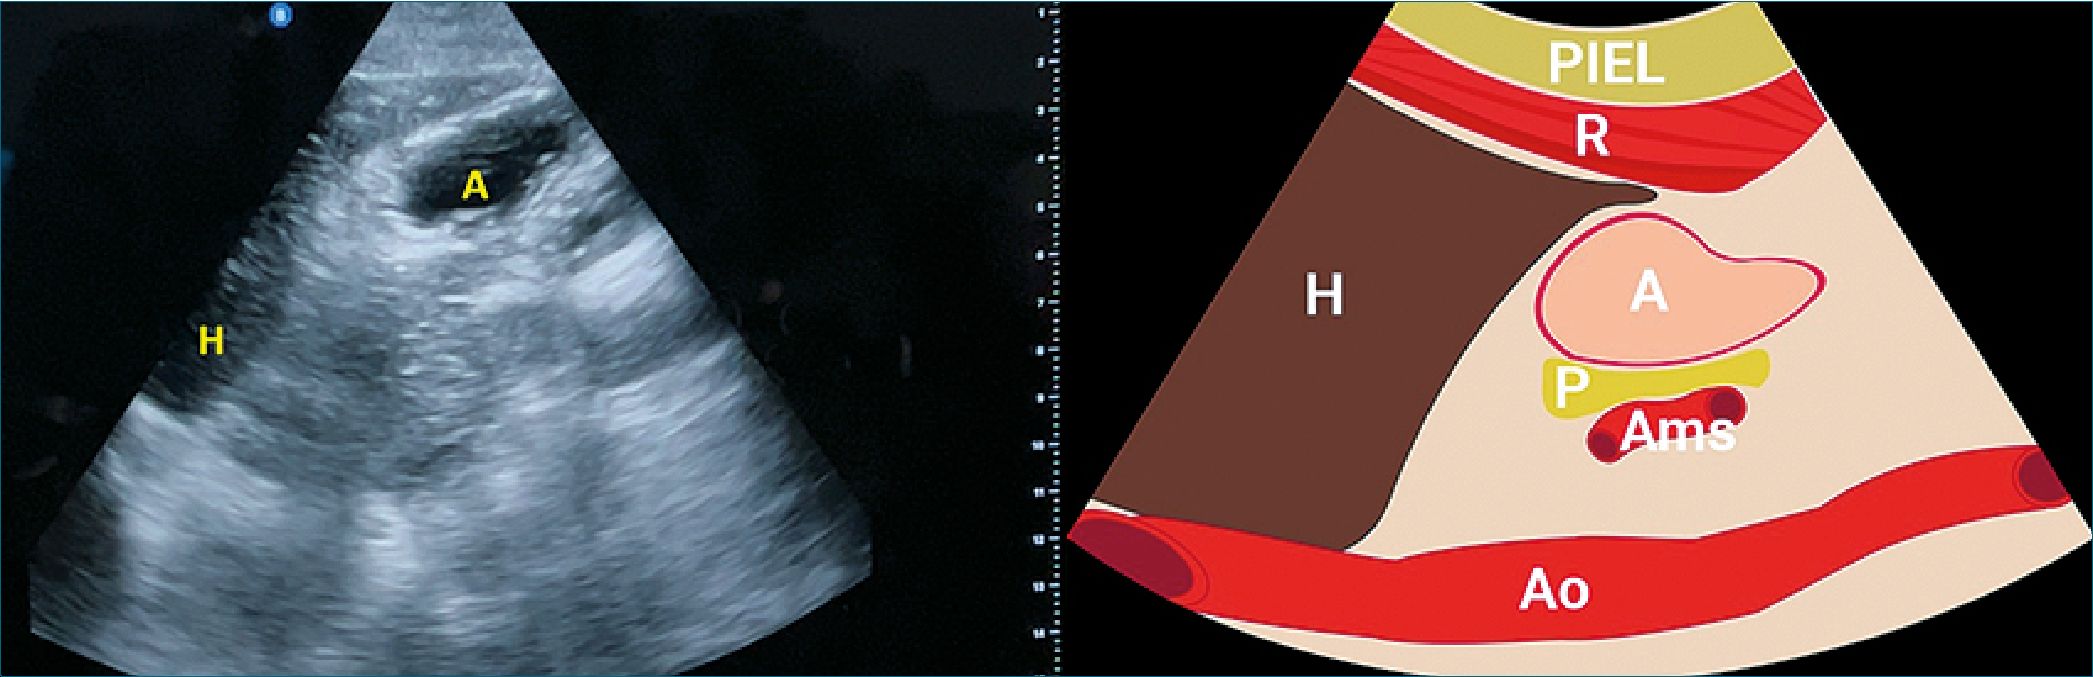

El antro gástrico se localiza inmediatamente debajo (caudalmente) del lóbulo izquierdo del hígado, que actúa como ventana acústica hacia el abdomen superior. Posteriormente, al antro gástrico se encuentran el cuerpo del páncreas, la arteria mesentérica superior y la aorta. Para obtener imágenes óptimas del antro, es necesario visualizar el borde inferior del hígado a nivel de la aorta en el eje longitudinal. La aorta puede identificarse como una estructura pulsátil discreta, situada de manera profunda al antro gástrico (Figura 2)[14]. La correcta identificación de estos puntos de referencia anatómicos asegura que las imágenes del estómago se obtengan dentro de un plano estandarizado y reproducible.

Detrás del borde del lóbulo izquierdo del hígado, se observa el antro gástrico vacío y colapsado, con su característica apariencia en forma de diana. Otros puntos de referencia importantes que se pueden visualizar en la imagen 2 incluyen la cabeza del páncreas, que generalmente se encuentra justo debajo del antro, seguida de la arteria mesentérica superior, y finalmente la estructura vascular profunda, que es la aorta.

Figura 2. Imagen representativa del plano que se debe obtener en la vista del ultrasonido.

Figura 5. Profundidad, ganancias y estructuras del ultrasonido gástrico. Lado izquierdo: Ultrasonido: H: Hígado; A: Antro gástrico: Lado derecho: imagen representativa; R: Recto abdominal; P: Páncreas; Ams: arteria mesentérica superior; H: Hígado; Ao: Aorta.